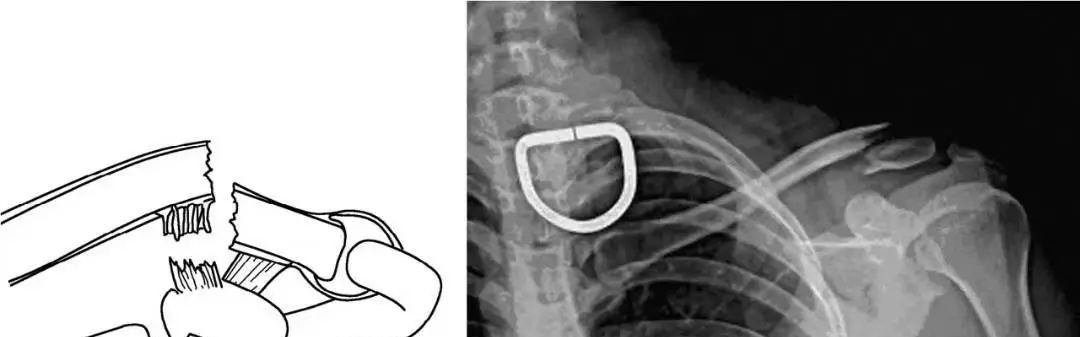

对于CraigⅡ、Ⅴ型不稳定锁骨远端骨折来说,造成不稳定的力量来自以下四个方面:上肢的重力,胸大肌、胸小肌和背阔肌的牵拉,肩胛骨的旋转,斜方肌对骨折内侧端向后上方的牵拉。以上因素使得不稳定的锁骨远端骨折非手术治疗的不愈合率可达到22%~33%。

手术治疗方法包括1~枚克氏针、螺纹针、螺丝钉经肩峰进行固定、喙锁螺丝钉固定、喙突移位、张力带以及接骨板等。目前多采用锁骨钩接骨板进行复位后的固定,该治疗方法具有固定物放置容易、可较为准确的维持复位、不破坏肩锁关节、内固定物相对稳定等优点,不会像传统的克氏针一样向周围组织发生滑移。但该治疗方式易导致患者在术后功能锻炼时产生的应力沿肩锁关节向锁骨传导,在接骨板的内侧部位造成应力集中,并出现应力骨折。

锁骨板有哪些【每周科普】锁骨骨折分中段、外段、内段,治疗方式也有差异_https://www.jmylbn.com_新闻资讯_第13张

锁骨钩接骨板内固定术后应力骨折